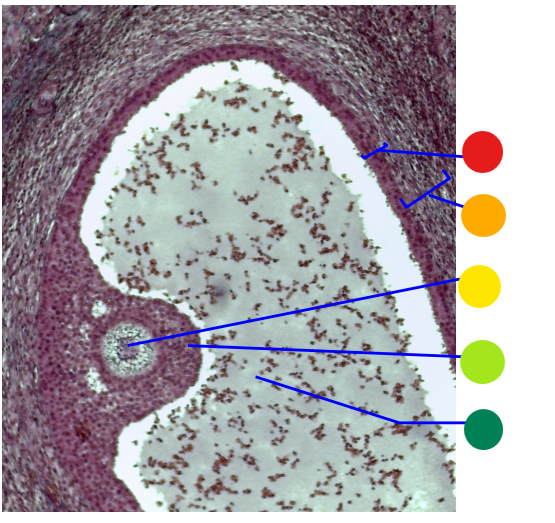

red

granulosa cells

orange

thecal cells

yellow

zona pellucida

What is this

secondary follicle

red

granulosa cells

orange

thecal cells

yellow

primary or secondary oocyte

light green

cumulus oophorus

dark green

antrum

what is this

tertiary follicle